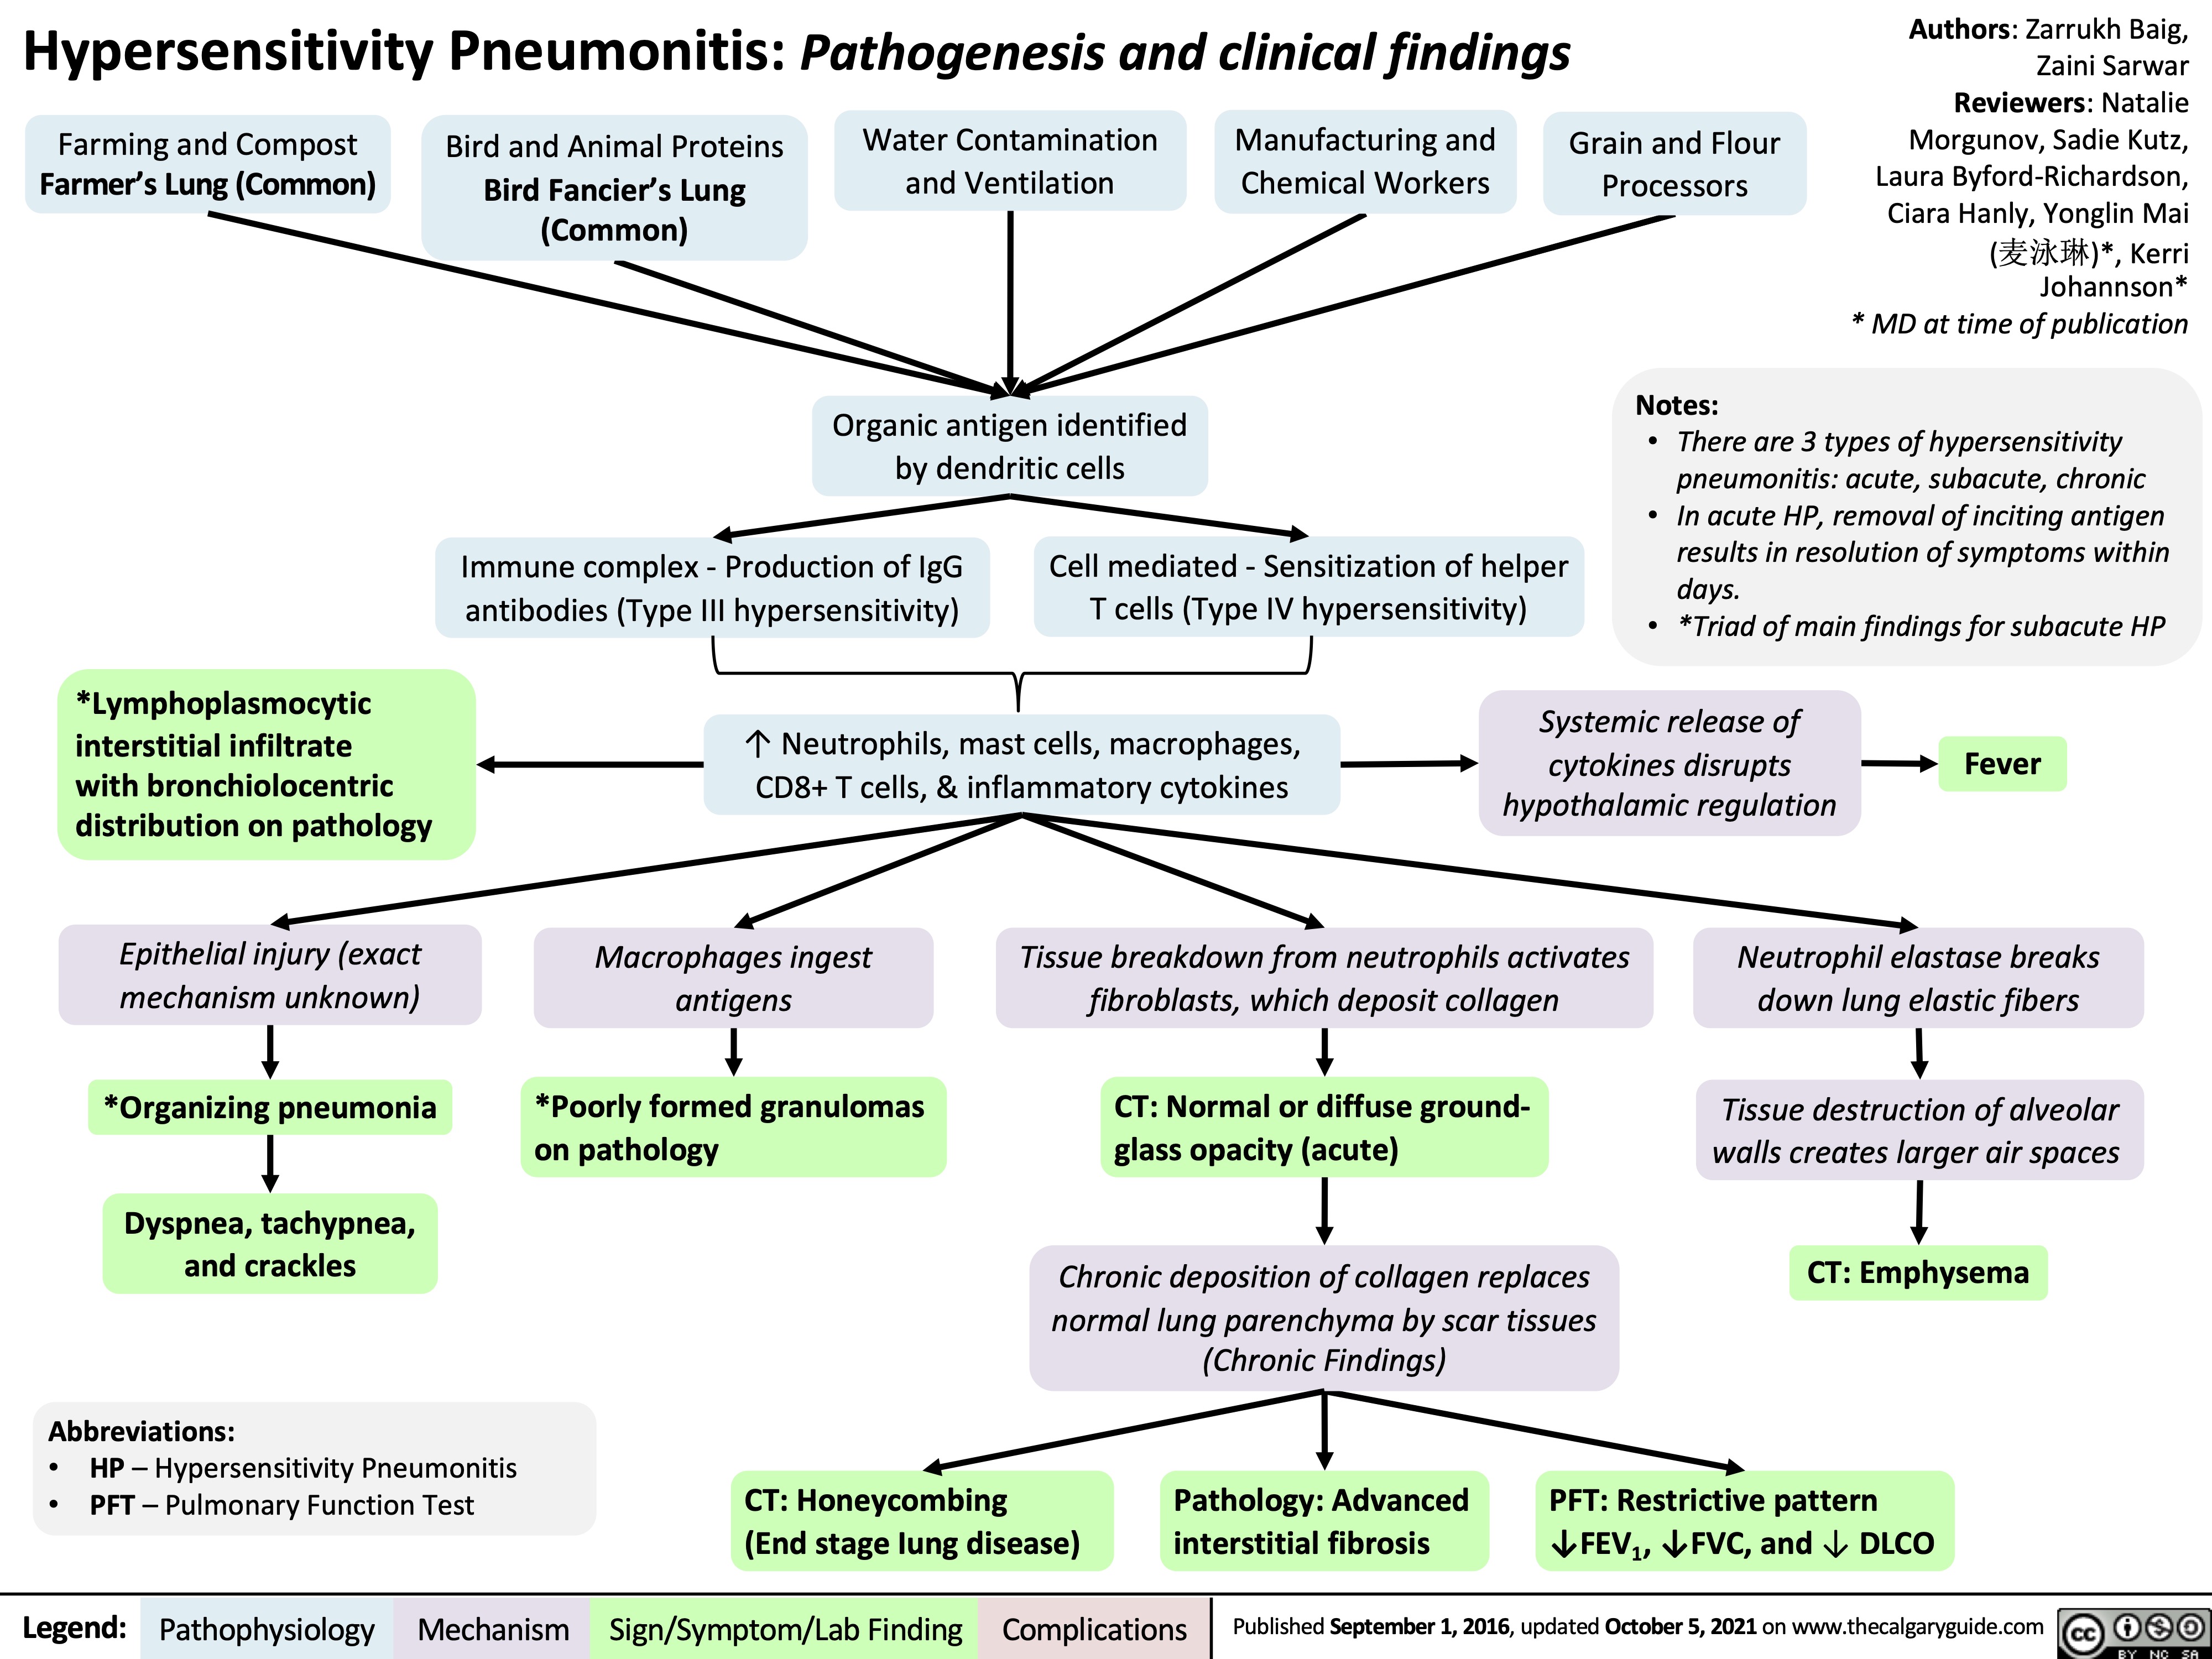

hypersensitivity pneumonitis

hypersensitvity pneumonitis - cause, features, dx, tx

inhalation of env/occupational antigens, usually animal (birds), fungi, bacteria, or inorganic chemicals leading to interstitual lung disease

acute - constitutional, flu-like sx, leukocytosisl; or more chronic - cough, dyspnea, fatigue, weight loss

diagnosed via hx & ct of chest showing fibrosis. also lymphocytosis on bronchoaleolar lavage, noncaseating granulomas on histopathology

avoid antigen, usually resolves spontaneously. can give glucocorticoids if symptoms persist. if refractory, may eventually require lung transplant